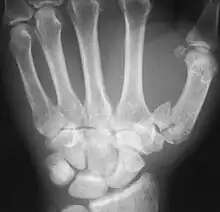

An X-ray showing a comminuted metacarpal bone fracture

2. (medicine) To cause fragmentation (of bone).

For example, comminuting fractures on ribs 4–8 along the rib angle most likely are associated to shots through the scapula, whereas injuries through or near to the costochondral articulation of the first rib could also be associated to wounds of the sternum or clavicle.

In the past, there have been controversies over the use of bone graft in comminuted fractures of the forearm.

When using reduction forceps, care must be taken to prevent comminuting the medial epicondylar fragment.